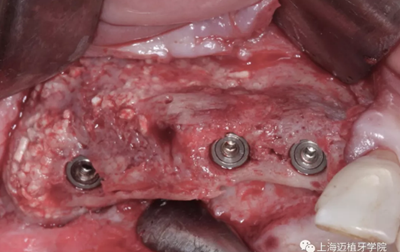

植入植體

成骨的效果非常好,植入時可以見血液外滲,血運良好

再過三個月后進(jìn)行軟組織處理,頂部復(fù)位瓣